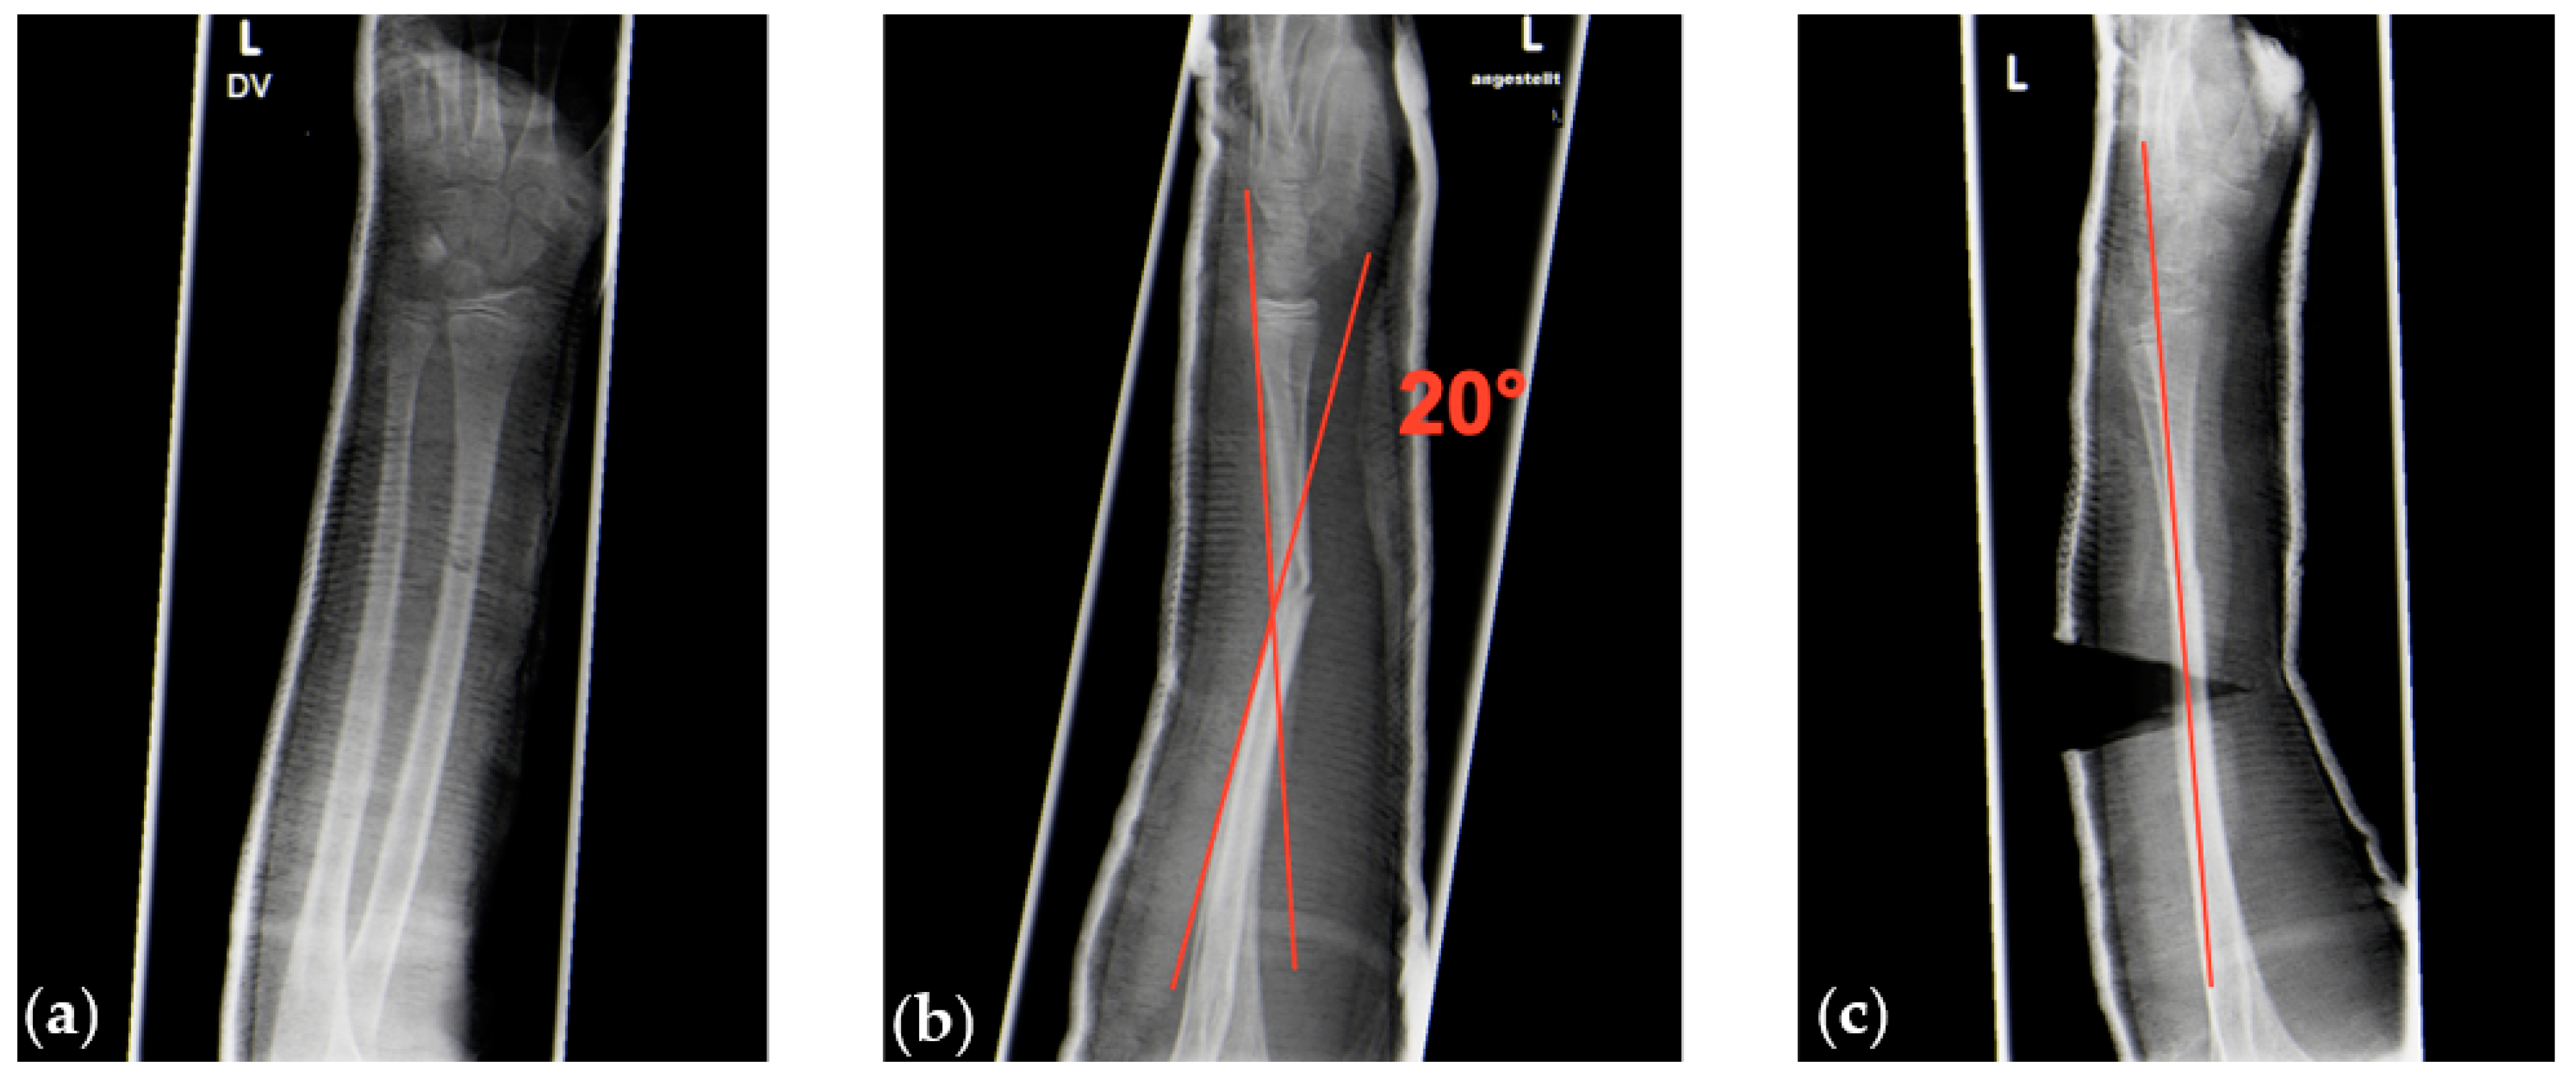

Among patients with marked displacement of bone fragments, 5 of 15 (33.3%) patients with overall angular correction of >15° reported a VAS score of ≥4 measured 3–5 min after stopping nitrous oxide/oxygen inhalation (Figure 5).

Figure 5. (a,b) Radiologic images of a sagittal 20° angular deformity of a greenstick fracture between midshaft and distal forearm shaft region without deformity in the coronal plane (a). (c) Complete correction of the deformity after cast wedging.